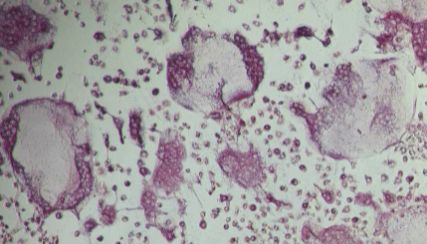

试剂、抗体、细胞库 / 细胞培养、ELISA 试剂盒、技术服务、耗材、实验室仪器 / 设备、体外诊断、论文服务